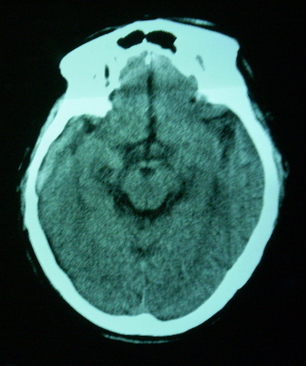

男,70岁,左侧肢体活动障碍口角向右侧歪斜2天,有高bp病史

pe:神情,能与之正常交流,吐字不清,180/90mmhg,双瞳孔无异常,左侧肢体肌力1级 b(+)

图中有个同心圆壮低密度影是ct伪影,见笑了。

1、右侧基底区及外囊区腔隙性脑梗塞。2、脑萎缩。

支持腔梗、脑萎缩